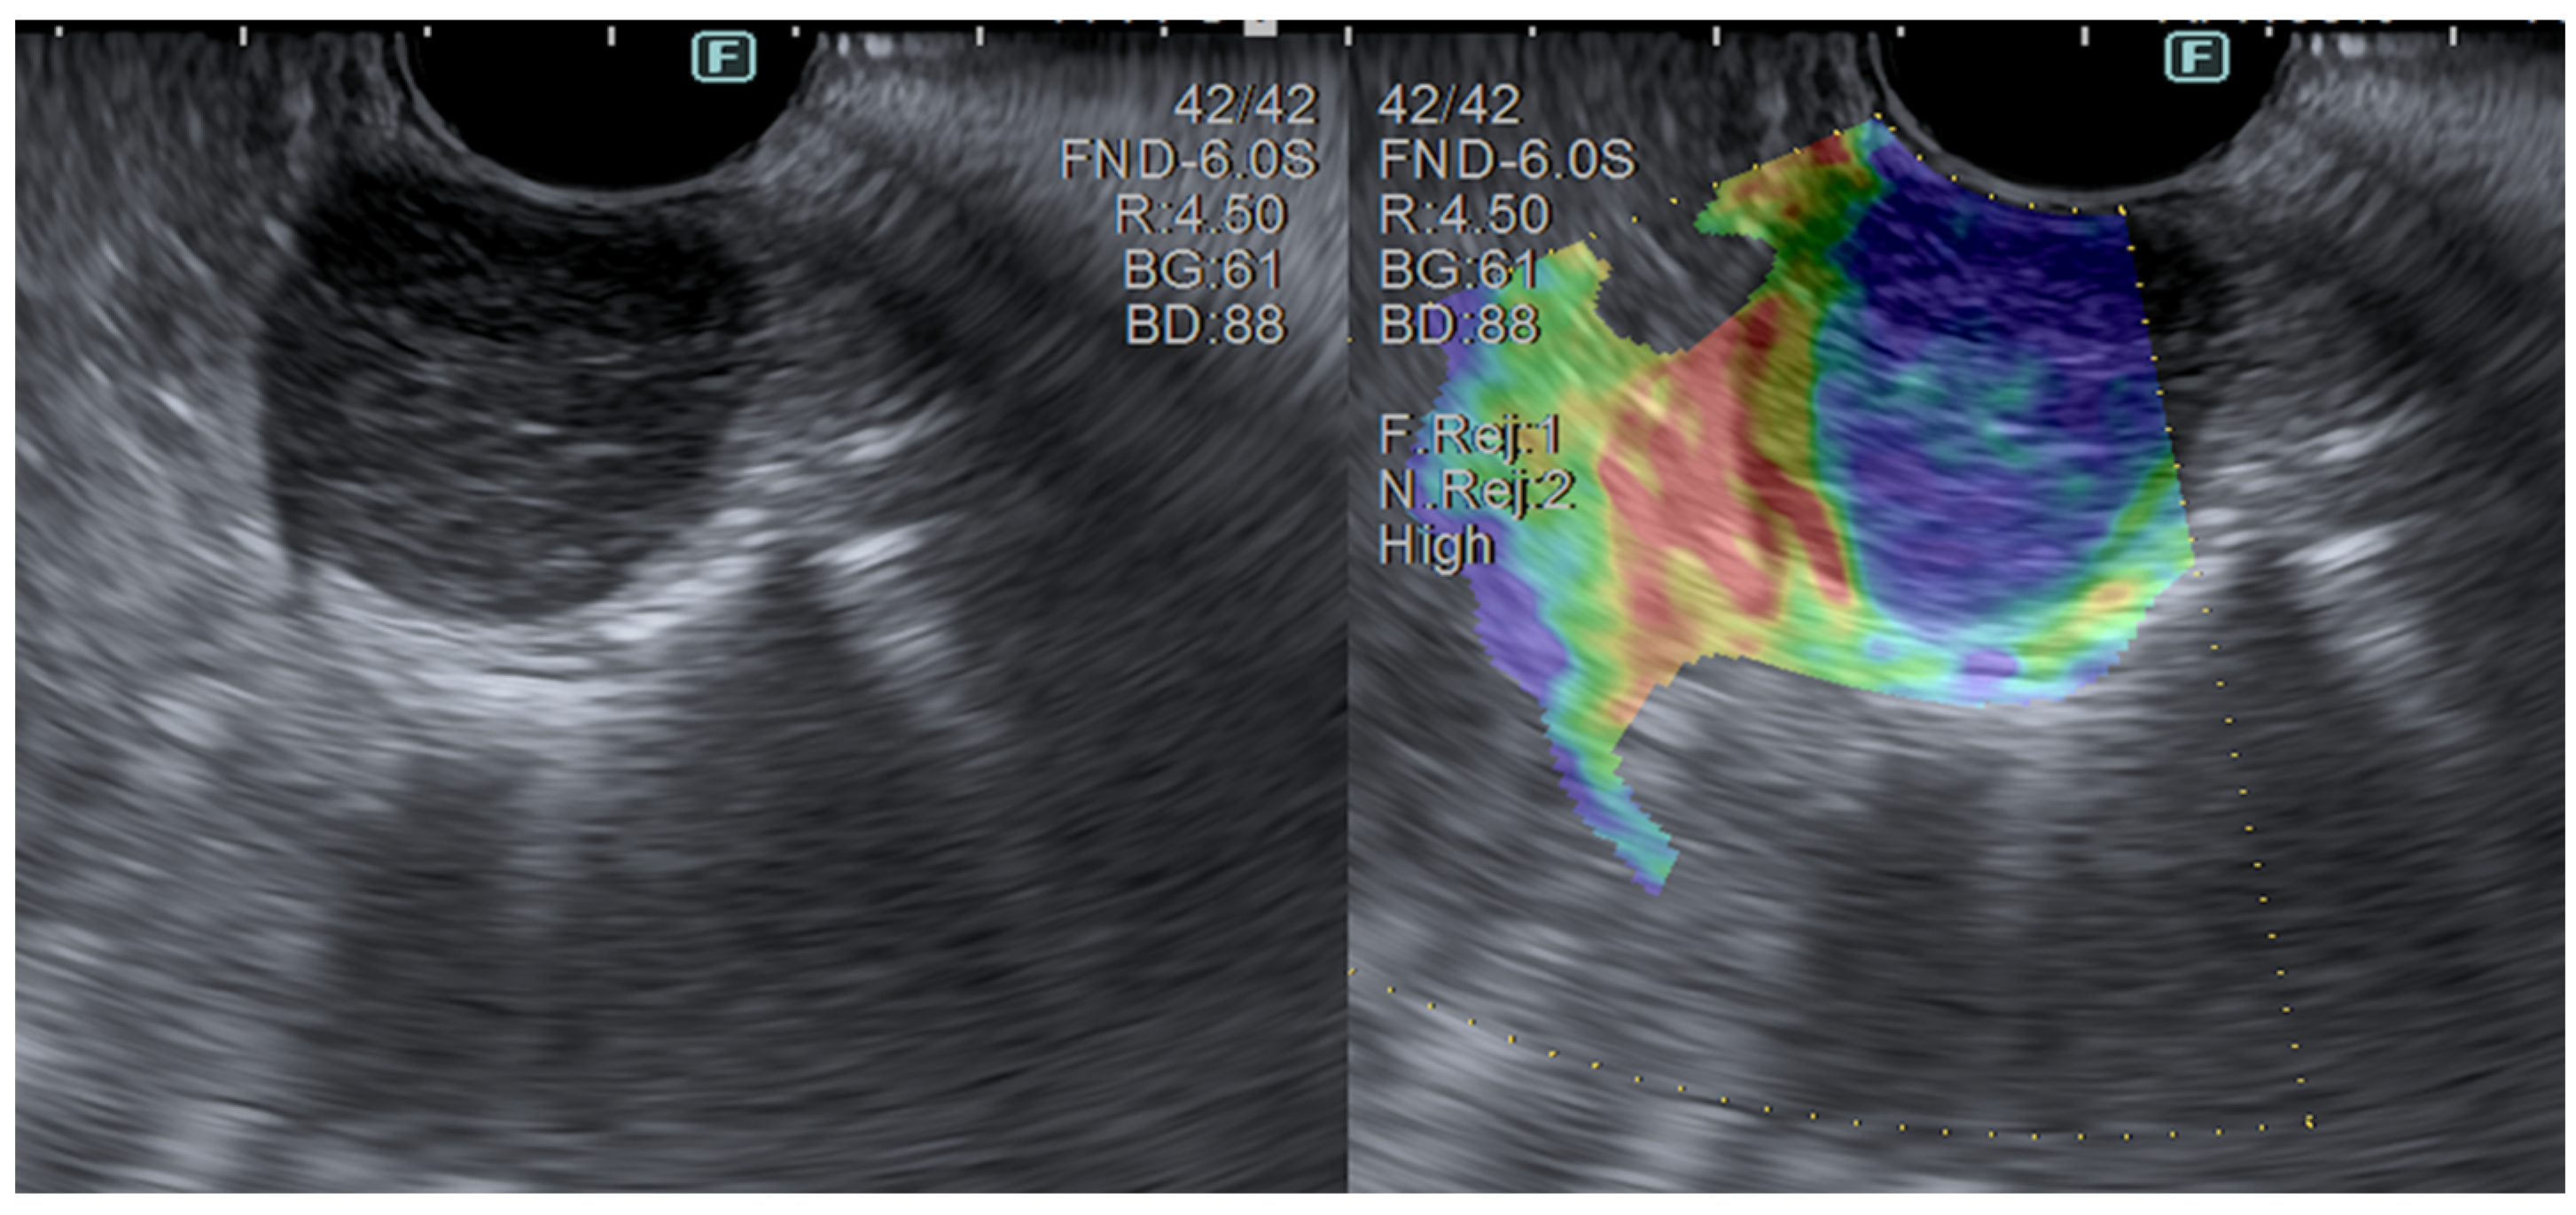

3.2. Elastography